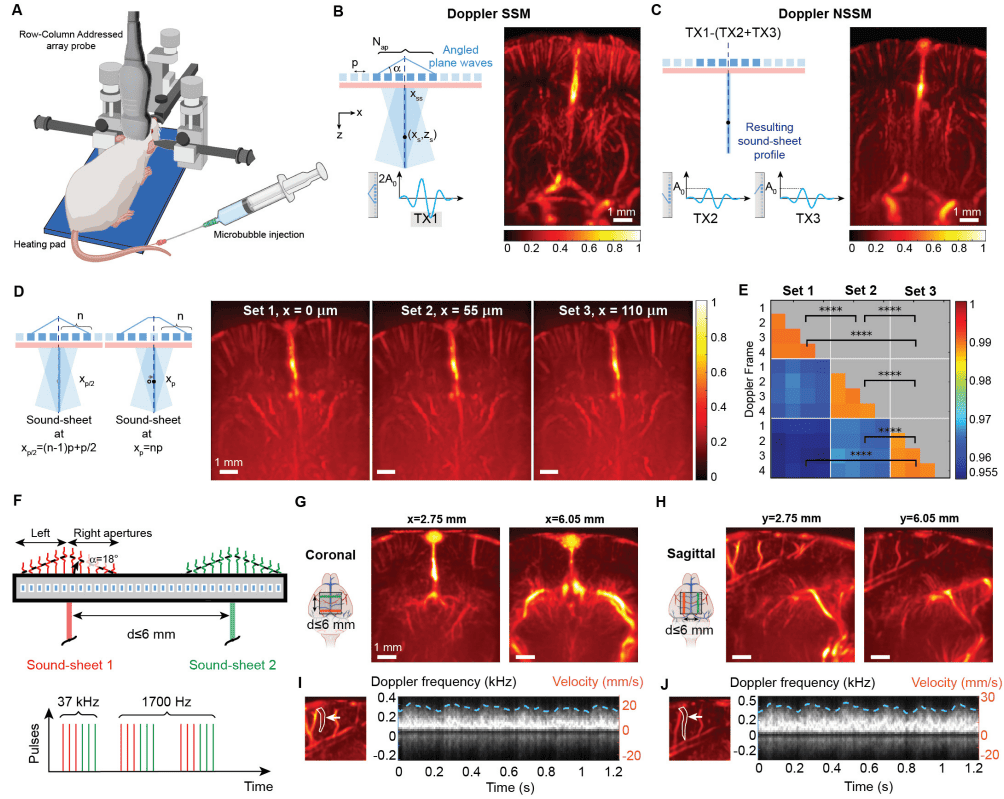

В парадигме NSSM субапертура элементов RCA-преобразователя Nap (1A) используется для передачи перекрестно распространяющихся ультразвуковых плоских волн или X-волн из двух соседних полуапертур под углами α и −α (1B). Эта пространственно структурированная ультразвуковая передача приводит к возникновению недифракционного поля акустического давления в плоскости XZ, демонстрирующего двойное акустическое давление вдоль главного лепестка луча, и плосковолнового акустического поля давления в плоскости YZ (1C).

Акустическое давление далее модулируется вдоль главного лепестка недифракционного луча с использованием последовательности импульсов перекрестной амплитудной модуляции (xAM от cross amplitude modulation) (1D), которая ограничивает нелинейное рассеяние тонким звуковым листом с постоянной шириной луча независимо от глубины (1E). Звуковой листовой луч простирается до глубины перекрестного распространения zcp = Nap / 2, которая обычно составляет порядка 100λ. 2D-изображения реконструируются из отраженных ультразвуковых эхо-сигналов, полученных на элементах ортогональной решетки RCA (1B), с использованием алгоритма формирования луча с задержкой и суммой.

Функции рассеяния точки (PSF от point spread function) резонансных MB сообщаются (1F) для линейной визуализации или SSM (т. е. только передача TX1) и NSSM (т. е. передачи TX1-TX2-TX3). Ученые выбрали MB в качестве нелинейных точечных целей при моделировании, а не GV, поскольку известны уравнения, регулирующие их вибрацию в ультразвуковом поле. Изображения SSM и NSSM в плоскости XZ показали схожие PSF, поскольку оба режима визуализации работают на одной и той же частоте (1G).

Для сканирования объема передачи звукового листа электронно перемещаются вдоль двух массивов RCA-преобразователя с использованием скользящей апертуры элементов (1H). Точность микросканирования (λ/2) достигается путем чередования передач с и без бесшумного элемента в центре субапертуры (1H), поскольку шаг (p) или межэлементное расстояние RCA приблизительно равно λ. 3D PSF представлены на 1I.

Было показано, что нелинейная визуализация снижает уровни вторичных лепестков 3D PSF на 12.8 дБ ± 4.4 дБ благодаря ограничению нелинейного рассеяния MB плоскостью звукового листа. С точки зрения разрешения, NSSM предоставил среднюю 3D функцию рассеяния точки 1λ х 0.6λ х 0.6λ по сравнению с 1λ х 0.9λ х 0.9λ для SSM (1J).

Наряду с генетически кодируемыми GV, синтетические липидно-оболочечные MB являются еще одним классом ультразвуковых контрастных агентов, используемых в качестве сосудистых репортеров. MB демонстрируют амплитудно-зависимое ультразвуковое рассеяние, что делает их также обнаруживаемыми с помощью последовательностей импульсов амплитудной модуляции. Чтобы проверить способность NSSM визуализировать MB, циркулирующие в кровеносных сосудах, ученые провели высокоскоростную нелинейную допплеровскую визуализацию сосудистой системы мозга крысы (снимки выше).

MB, настроенные на высокочастотный ультразвук, вводились посредством инъекций в хвостовую вену анестезированным крысам с фиксированной головой (4A). В качестве справочного материала линейные допплеровские изображения SSM были получены с частотой кадров 4.4 кГц (4B) и дали результаты, аналогичные сверхбыстрым допплеровским изображениям мозга крысы. Допплеровские изображения NSSM (4C) были получены с использованием амплитудно-модулированных данных и фильтра верхних частот для удаления остаточных статических эхо-сигналов.

Поскольку нелинейная допплеровская обработка пространственно ограничивает данные изображения тонкой звуковой плоскостью размером 100 мкм x 9.6 мм x 8.8 мм, было обнаружено меньше сосудов на 4C, чем на 4B, который проецирует на одно изображение эхо-сигналы, возникающие из косых путей каждой плоской волны (1C). В результате кортикальная поверхность была четко очерчена в допплеровском NSSM (4C), тогда как сосудистые сигналы, проецируемые из косых путей каждой плоской волны, видны над корой на 4B.

Затем ученые провели ультразвуковое секционирование сосудов мозга крысы с субволновыми шагами сканирования 55 мкм (4D), получив четыре последовательных допплеровских сбора данных на плоскость. Была проведена количественная оценка сосудистых изменений в этих смежных плоскостях путем вычисления значения матрицы индекса структурного сходства для каждого допплеровского сбора данных (4E). Внутри наборов индекс структурного сходства в среднем составил 0.99. Это указывает на то, что сосудистые изображения были почти идентичными на протяжении сердечных циклов. Между наборами индекс снизился до 0.96. Это подтвердило, что наблюдались две отдельные сосудистые плоскости.

Вдохновленные методами многослойной томографии, ученые проверили способность допплеровской NSSM захватывать несколько видов мозга одновременно. Для этого ученые чередовали передачу импульсной последовательности с использованием двух субапертур элементов массива (4F). В этой конфигурации частота визуализации была установлена на 1.7 кГц в обеих плоскостях звукового листа. Чтобы продемонстрировать универсальность этого подхода, была проведена визуализация двух коронарных сосудистых плоскостей, разделенных на 3.3 мм, с помощью первой решетки RCA-преобразователя (4G). Аналогичным образом были визуализированы две сагиттальные сосудистые плоскости, разделенные на 3.3 мм, с помощью второй решетки RCA-преобразователя, в результате чего были обнаружены симметричные сосудистые плоскости в каждом полушарии (4H). Наконец, допплеровские спектрограммы SSM в каждой сагиттальной плоскости были обработаны, чтобы показать, что получение данных было непрерывным и совпадало во времени (4I–4J). Частота сердечных сокращений, полученная с помощью допплерографии, составила 298 и 295 ударов в минуту в каждом полушарии мозга соответственно.